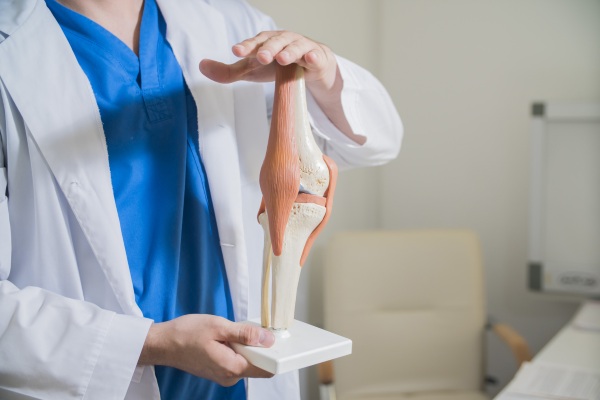

По форме сочленение относится к мыщелковым. В его формировании участвуют 3 костные структуры, поэтому сустав называют сложным. В коленном суставе сочленяются мыщелки бедра, суставная поверхность большеберцовой кости и надколенник. Малоберцовая кость в состав колена не входит.

Сочленение относят к сложным. Это связано с тем, что количество соединяемых костей более 2.

В коленном суставе 3 кости. Это большеберцовая, бедренная, которые относятся к длинным трубчатым костям, и сесамовидная кость — надколенник.